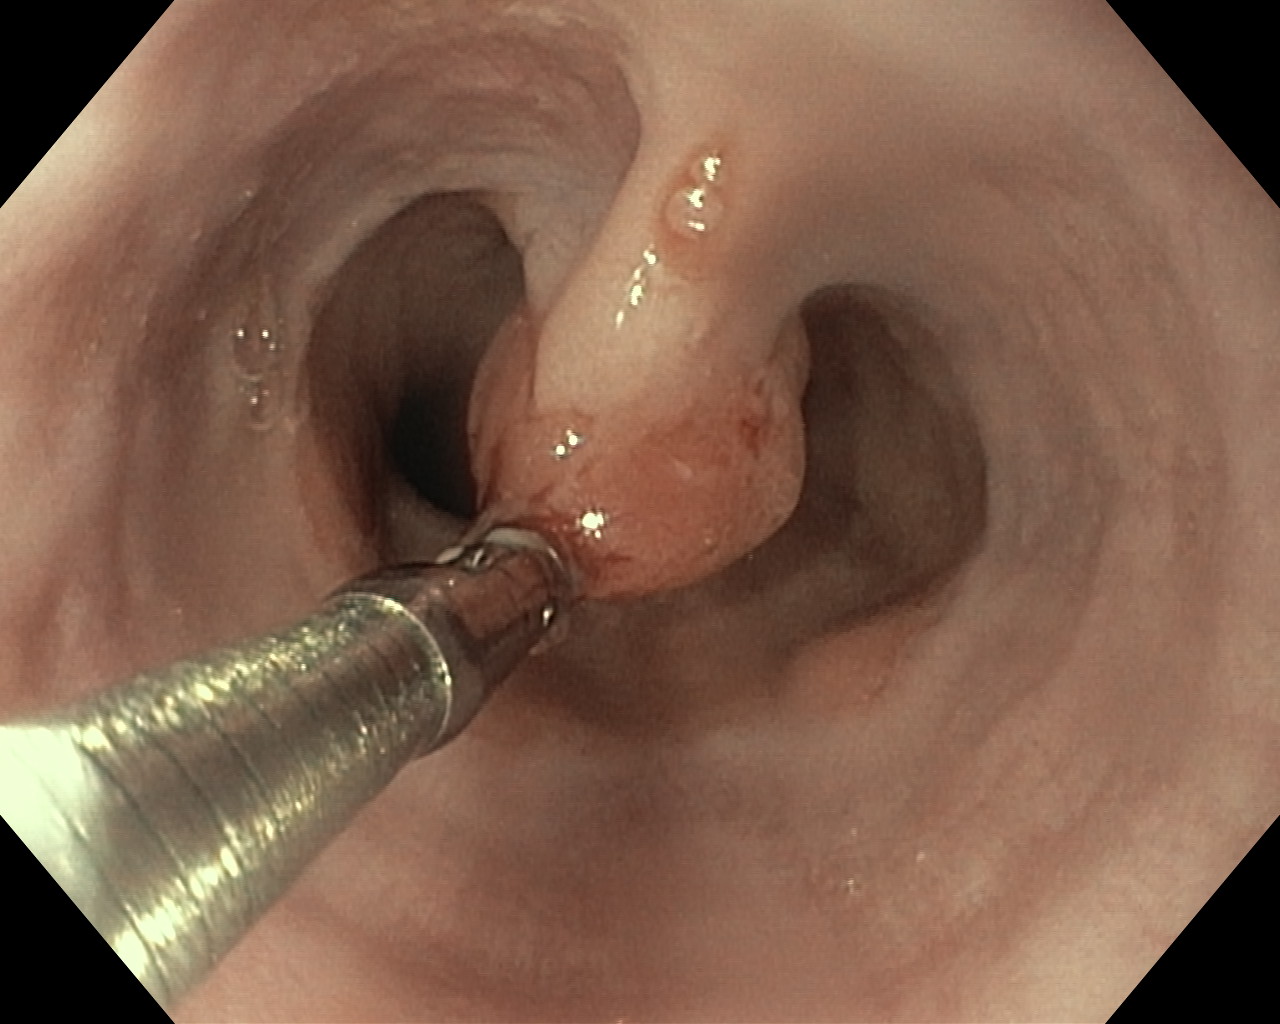

Polipy

Zabiegi endoskopowe